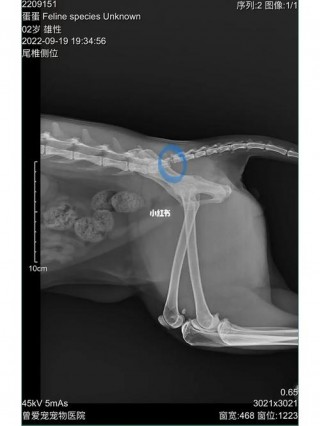

猫咪尾巴骨折了怎么办,(猫的尾巴骨折了对猫有什么影响)

猫咪拍片多少钱,猫咪去拍片子要多少钱?

这篇文章给大家聊聊关于猫咪拍片多少钱,以及猫咪去拍片子要多少钱对应的知识点,希望对各位有所帮助,不要忘了收藏本站哦。猫咪拍片子大概需要多少钱〖One〗、猫咪拍片子的费用通常在200『8』00元之间浮动,费用差异主...

猫咪骨头断了能自愈吗?猫咪骨头断了能自愈吗图片(最新)

大家好,今天小编来为大家解答猫咪骨头断了能自愈吗这个问题,猫咪骨头断了能自愈吗图片很多人还不知道,现在让我们一起来看看吧!猫股骨头断了能自愈吗猫咪盆骨和股骨头骨折不能自愈。以下是具体分析:盆骨骨折:猫咪盆骨骨折后...